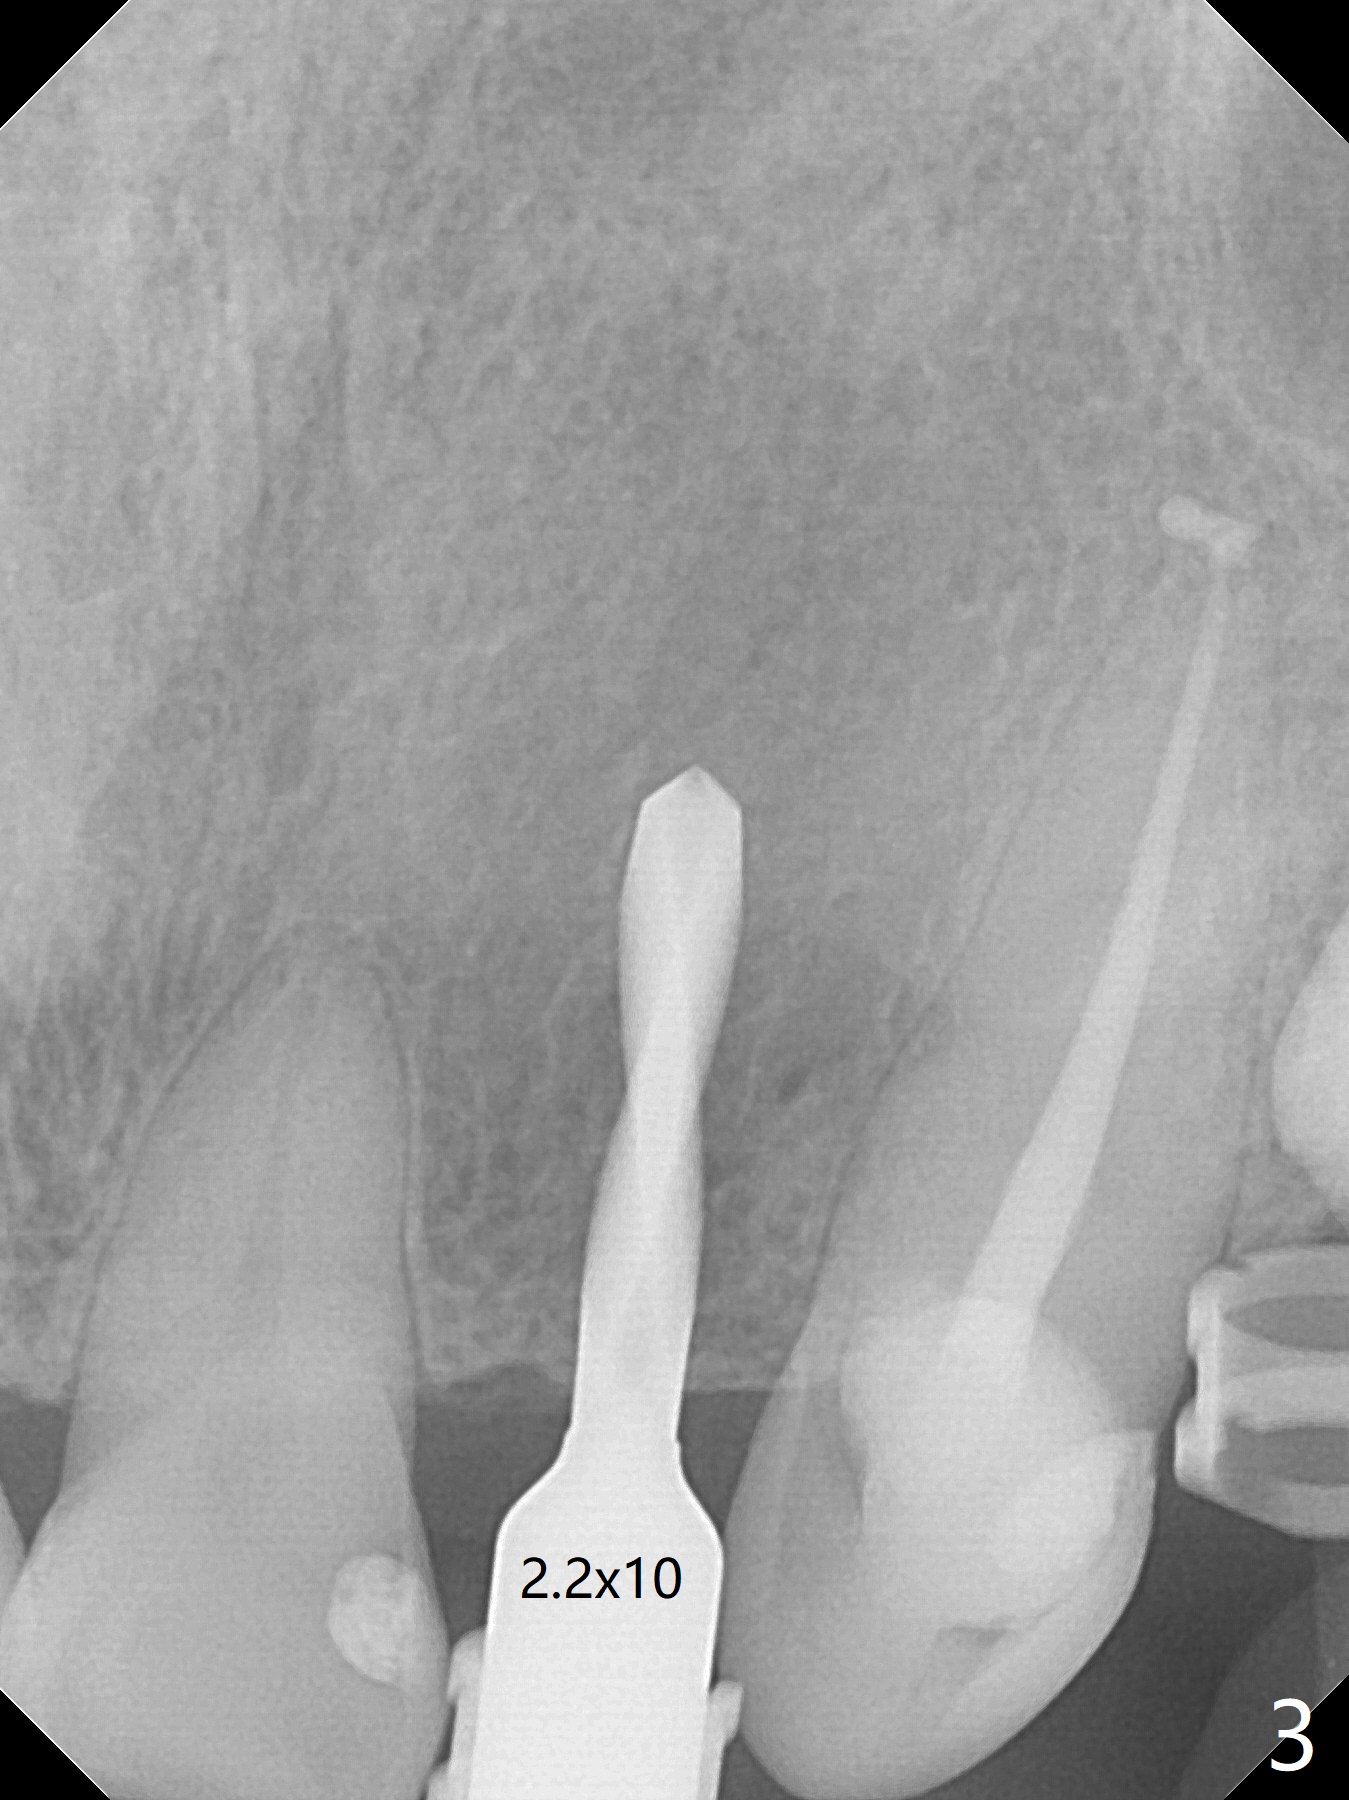

The patient has gummy smile (Fig.1).  The edentulous ridge at #10 has buccal concavity (Fig.2 *).  The surgical guide fits well without #9 distal trimming.  With 34 mg Xylocaine and 17 mcg Epinephrine infiltration at #10 and 12, the patient feels pain when 2.2 (in fact 1.9) x8.5 mm drill is being used.  When Septocaine is added, the osteotomy at #10 is found distal.  Out of curiosity, PA is taken with 2.2x10 mm drill in place; its trajectory seems satisfactory (Fig.3).  When a 2.5x13 mm 1-piece implant is placed free hand, it deviates palatal, which is confirmed with incision after addition of 34 mg Xylocaine and 34 mcg Epinephrine.  A new osteotomy is created by S-Mini Kit buccal to the previous one.  With Lindamann bur to adjust the position of the new osteotomy twice, the last drill (2.0 mm) apparently starts to perforate the apical portion of the buccal plate.  The perforation seems to enlarge when the mini implant is re-placed (Fig.4, 8 (green area) <30 Ncm).  With Vanilla graft (Fig.8 pink circles) and abutment height adjustment (Fig.4), a provisional is fabricated with occlusal clearance.  There are two reasons for failure of the surgical guide: failure to trim the tooth #9 distal (minor palatal guide displacement, Fig.5) and deflection of pointed drill and 2.2 mm drills over the hard palatal plate slope (Fig.6).  To avoid this complication, the pointed drill should be done free hand initially, after incision and obliquely (Fig.7).  The guide is placed to finish the rest of osteotomy if deem to be appropriate.